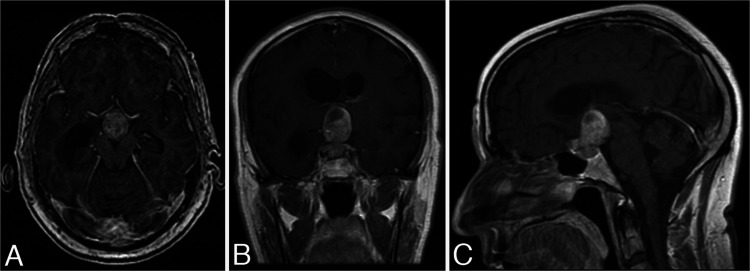

A 66-year-old male patient came to the emergency department displaying confusion and imbalance. He had a bitemporal hemianopsia on examination. Endocrine laboratory tests showed no apparent hormonal disturbances. His initial brain computed tomography scan showed a 2.1 × 1.9–cm heterogeneous mass in the sellar and suprasellar region that was exerting a mass effect upon the anterior third ventricle and causing obstructive hydrocephalus. Magnetic resonance imaging (MRI) showed a 3.8 × 2.1 × 2.4–cm, heterogeneously enhancing mass consistent with a pituitary macroadenoma (Fig. 1). The tumor contained hemorrhage and necrosis within the suprasellar component, and it had slight extension into the right cavernous sinus. Having the impression that the tumor was a pituitary macroadenoma, we completely removed it through an endoscopic transsphenoidal resection (Fig. 2). A vascularized nasoseptal flap and an abdominal fat graft were used to prevent postoperative cerebrospinal fluid leakage. Histopathological examination confirmed the diagnosis of an NPA (Fig. 3A). Immunohistochemical stains showed PA cells that were patchily positive for adrenocorticotropic hormone, whereas they were negative for prolactin, growth hormone, thyroid-stimulating hormone, luteinizing hormone, and follicle-stimulating hormone. The patient had an excellent recovery with normalization of his vision and mental status, although the hypopituitarism remained and was corrected with medication. He was followed up for four years, including serial MRI, but stopped coming for routine examinations after that point.

FIG. 1.

Initial preoperative MRI. Axial (A), coronal (B), and sagittal (C) contrast-enhanced T1-weighted images. A 3.8 × 2.1 × 2.4–cm, heterogeneously enhancing sellar and suprasellar mass is visible, most suggestive of a pituitary macroadenoma. The tumor contains hemorrhage and necrosis within the suprasellar component, and it has slight extension into the right cavernous sinus.